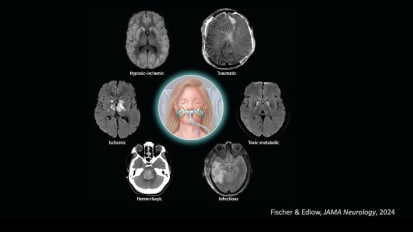

Dr. Fischer describes a framework for reasoning through neuroprognostication in disorders of consciousness, reviewing key principles and the state of the field in prognostic testing.The Goldilocks Approach to Normothermia Management: Not too hot - Not too cold just right!